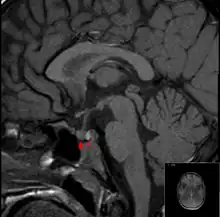

The diagnosis is achieved with magnetic resonance imaging and blood tests. Treatment is by the timely correction of hormone deficiencies. In many cases, surgical decompression is required. Many people who have had a pituitary apoplexy develop pituitary hormone deficiencies and require long-term hormone supplementation. The first case of the disease was recorded in 1898.[1]

It is recommended that magnetic resonance imaging (MRI) scan of the pituitary gland is performed if the diagnosis is suspected; this has a sensitivity of over 90% for detecting pituitary apoplexy; it may demonstrate infarction (tissue damage due to a decreased blood supply) or hemorrhage.[1] Different MRI sequences can be used to establish when the apoplexy occurred, and the predominant form of damage (hemorrhage or infarction).[2] If MRI is not suitable (e.g. due to claustrophobia or the presence of metal-containing implants), a computed tomography (CT) scan may demonstrate abnormalities in the pituitary gland, although it is less reliable.[1] Many pituitary tumors (25%) are found to have areas of hemorrhagic infarction on MRI scans, but apoplexy is not said to exist unless it is accompanied by symptoms.[1][4]